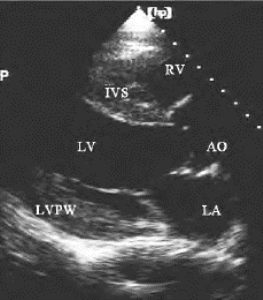

图21-5 高血压心脏病代偿期二维超声图

左室长轴切面室间隔与左室后壁肥厚,比例接近1。LVPW左室后壁,IVS室间隔